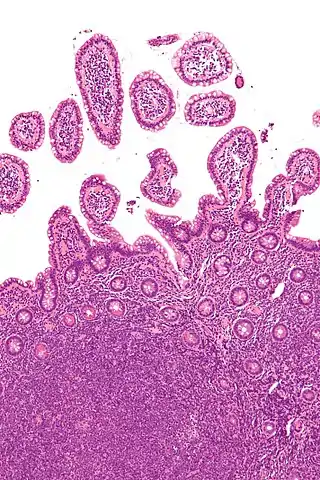

![]() Micrografía de un linfoma de células de manto (tipo de linfoma no hodgkiniano) en una biopsia de íleo terminal, tinción H&E. | ||